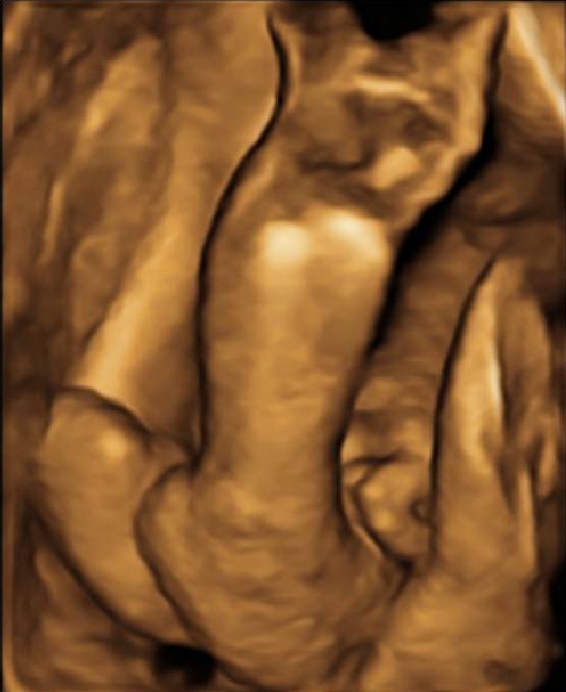

Le cause non sono ancora completamente conosciute, si pensa ad un’alterazione con attivazione dei geni responsabili della malattia che agisce durante la 12-16esima settimana di vita fetale (o di gravidanza). La diagnosi può essere fatta già in gravidanza attraverso l’esame ecografica. Ciò consente un adeguata informazione sulla patologia e sulle possibilità terapeutiche, nonché un trattamento precoce e adeguato che, se condotto da mani esperte evita il rischio di recidive.

Fig. 2 Foto piede torto in ecografia pre-natale